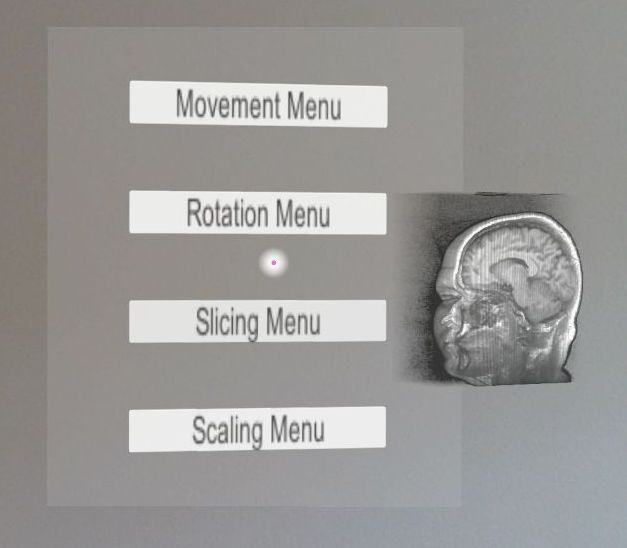

At this moment we have a basic yet functional UI which allows movement, rotation and scaling of the 3D medical volumetric image visualized. These scripts are acting directly on the data cube.

Another set of scripts which activates on the shader level allows volume slicing and image luminosity adjustments. A sample visualization is presented in Figure 4.5.